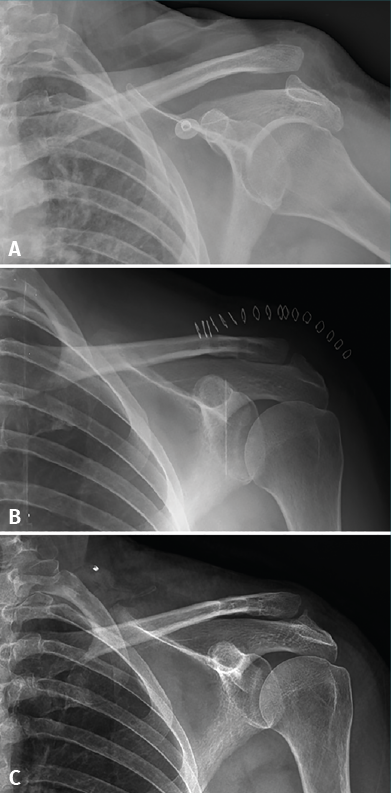

The two patients in which initial correct reduction of the joint was not achieved were seen to group most of the complications. The first patient, a 52-year-old woman with type IV acromioclavicular dislocation operated upon after four weeks of pain and dysfunction refractory to conservative management, presented insufficient reduction (54% displacement), progressive loss of reduction (finally 132%) and a poor functional outcome 14 months after surgery (Constant-Murley = 54; Quick-DASH = 69; ASES-shoulder = 57) - with evident scapular dyskinesia and clear anteroposterior and craniocaudal instability of the distal clavicle (Figure 3). The patient declined any other additional procedures. The second patient, a 50-year-old man with type V acromioclavicular dislocation subjected to conservative management during four months without success, presented initially insufficient reduction (43%) with progressive loss of reduction (74% at the end of follow-up), osteolysis of the distal clavicle and widening of the proximal orifice of the clavicle to 7.7 mm. These findings nevertheless had no functional repercussions, since after 18 months of follow-up the functional outcome was very good (Constant-Murley = 94; Quick-DASH = 88; ASES-shoulder = 99).

Figure 3. A 52-year-old woman with type IV acromioclavicular dislocation (A) subjected to surgery four weeks after injury due to refractory pain and dysfunction. The surgical outcome was considered acceptable, though with insufficient reduction (B). Fourteen months after surgery, the patient suffered persistent symptoms and loss of reduction was seen to have progressed (C).